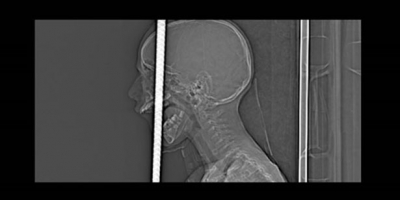

BAŞINA DEMİR ÇUBUK SAPLANAN ÇOCUĞUN SAĞLIK DURUMU İYİ

Zonguldak’ta kafasına demir saplanması sebebiyle Bülent Ecevit Üniversitesi Uygulama ve Araştırma Merkezine sevk edilen 7 yaşındaki Fırat Başaran’ın başındaki 1 metre uzunluğundaki

KAFASINDAKİ DEMİR AMELİYATLA ÇIKARILDI

Zonguldak’ta bisikletiyle gezerken 5 metre yükseklikten düşen 7 yaşındaki Fırat Başaran’ın ağzından giren demir başından çıktı.

DEMİR ÇUBUK KÜÇÜK ÇOCUĞUN KAFASINA SAPLANDI

Zonguldak'ta 7 yaşındaki çocuk evinin önünde bisiklete binerken yaklaşık 5 metre yükseklikten düşerek kafasına demir çubuk saplandı.